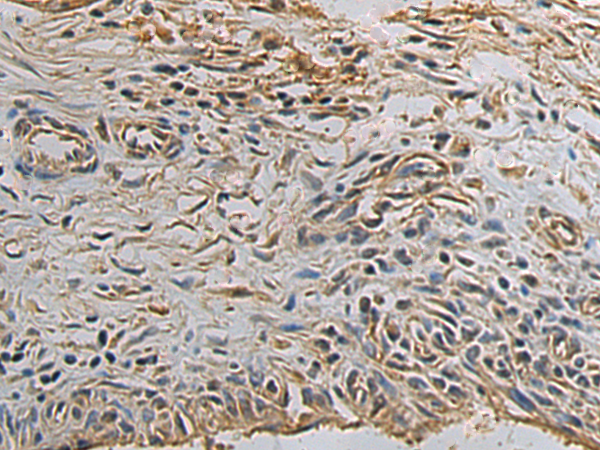

分类: 科研抗体货号: P09954别名: a1; Stv1; VPP1; Vph1; ATP6N1; ATP6N1A应用: IHC反应种属: Human, Rat